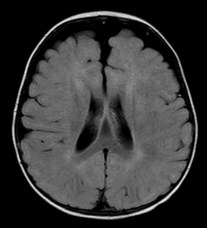

l’IRM identifie les veines et distingue l’épanchement sous-arachnoïdien du sous-dural qui lui est parfois associé. elle permet aussi de distinguer les macrocranies essentielles vraies des autres causes de macrocrânie : macrocéphalie vraie (syndrome de Sotos)

ici, macrocrânie révélatrice d’un déficit de l’oxydation des acides gras à chaînes courtes (SCAD)